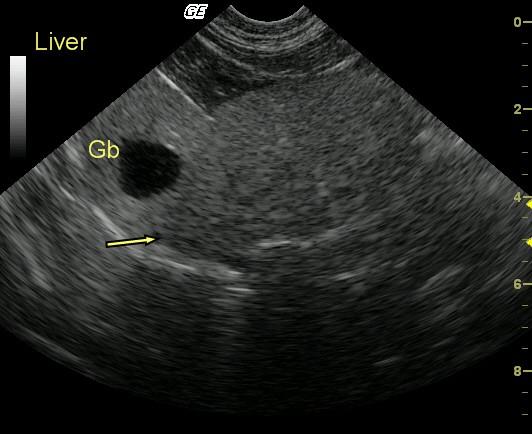

This 10 year old FS DLH cat presented for lethargy and anorexia. Physical examination revealed mild dehydration, poor coat quality, and mild jaundice. Blood analysis revealed moderately elevated SAP and moderately elevated total bilirubin.